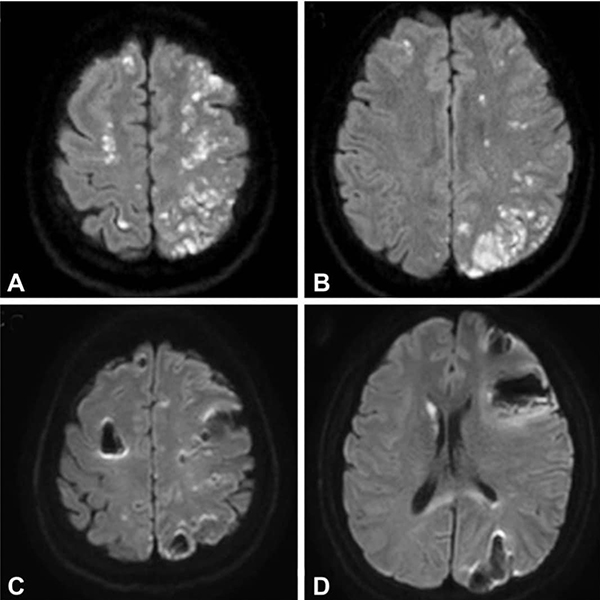

ภาพประกอบไม่เกี่ยวข้องกับข้อมูล